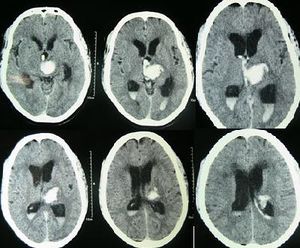

| استسقاء المخ كما يظهر في الأشعة المقطعية على المخ. المناطق السوداء في منتصف المخ هي تضخم غير طبيعي ومملوء بالسوائل. | |